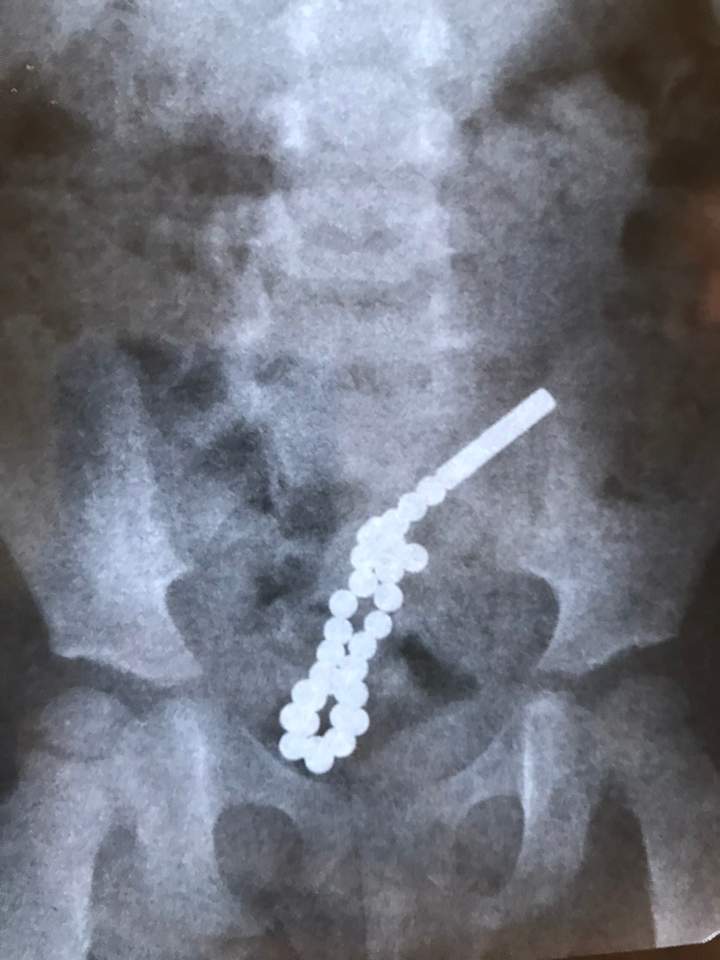

Як повідомив дитячий хірург Дмитро Грицак, дівчинці 2 роки і сім місяців. До лікарні потрапила зі скаргами на біль у животі. Рентген показав, що дитина ковтнула магнітні кульки, які потрапили у кишкіник і там з’єдналися між собою. Дістати їх було нереально, тож доводилося робити операцію традиційним способом – через розріз на животі.

“Ці неодимові магнітики дуже потужні. Дитина проковтнула 31 таку магнітну кульку. Частина з них потрапила в одну петлю кишківника, інша – в другу. У кишківнику вони між собою з’єдналися і пробили сім дірок у стінках кишечника”, – розповів Дмитро Грицак.